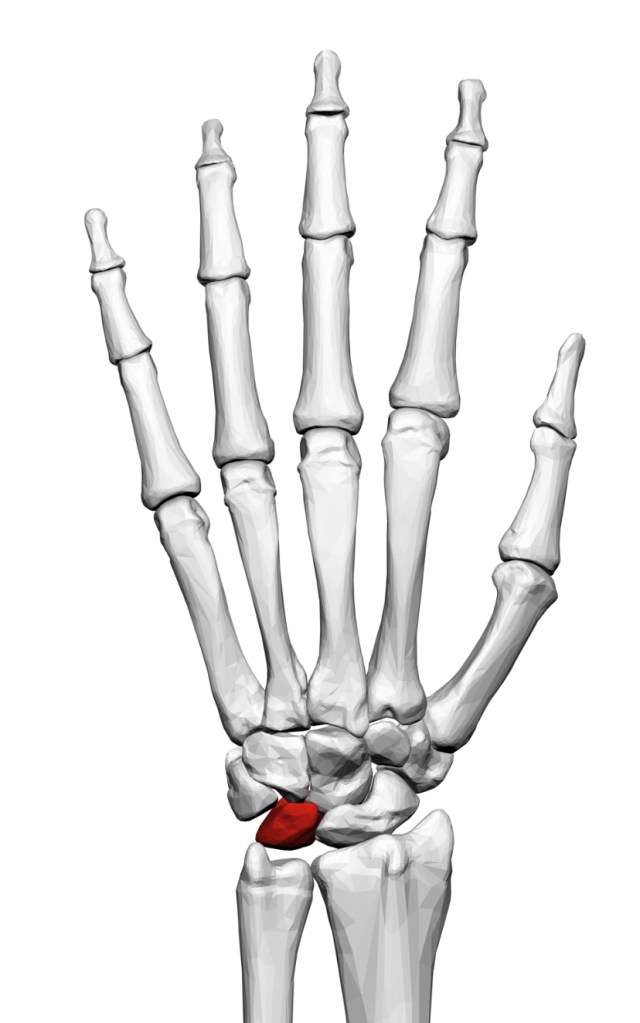

Where is the lunate bone?

The lunate bone is one of 8 bones which make up the wrist joint, and is situated right at the centre of the wrist.